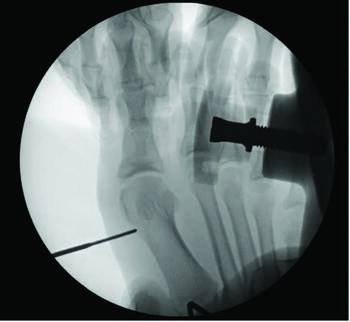

Documentation of surgical correction of hallux valgus first occurred in the early 1800s, with the earliest reports of percutaneous correction in the 1940s. Podiatric physicians experienced surgical restrictions at this time, and MIS provided an avenue for circumvention. Complications arose due to a lack of supportive means, and these outcomes led to an abrupt return to open procedures. The 1960s provided power equipment development and intraoperative fluoroscopy, which significantly improved outcomes of both open and percutaneous procedures. With the arrival of these modern tools, surgeons began to revisit the utilization of percutaneous procedures towards the end of the millennia. A subcapital osteotomy technique reported by Bosch, and “Simple, Effective, Rapid, Inexpensive,” modified by Giannini in the early 2000s, implemented a modern look at MIS hallux valgus procedures.8,9 Most recently, a guide to the percutaneous bunionectomy written by Siddiqui in 2014, and MIS radiographic outcomes in 2016, provided another available tool to surgeons, which decreased the complication rates and expanded the confidence in utilization of MIS bunion correction universally.10

Although minimally invasive hallux valgus surgery is a more modern technique, especially for the pediatric population, it still relies, in my experience, on AO principles of fracture fixation, including anatomic reduction in the first intermetatarsal and hallux abductus angles, stable fixation, preservation of blood supply, and early active mobilization. I find the percutaneous approach allows the reduction of a wide range of mild to severe radiographic angles and preservation of blood supply. In a study of minimally invasive bunion procedures, surgeons achieved up to a 12.5 degree correction of the first intermetatarsal angle and reported a 5.3 percent reoperation rate. The study was from a surgeon’s first 94 MICA procedures, and the author challenged the previously reported steep learning curve, citing low complication rates and ease of reproducibility.13

One can allow early mobilization by immediate weight-bearing in the postoperative course, most notably providing a decrease in adhesions and consequent stiffness of the joint. Another advantage includes multiple viable fixation options, including splintage with a Steinmann pin through external fixation. Many long-term risks of internal fixation include foreign body reaction, growth disturbance, chronic infection, corrosion, implant migration, and potential interference in orthopedic treatment later in life.14 Schmittenbecher and coworkers described risks of implant removal in children with various fixation options, concluding that each patient’s treatment selection must weigh the benefits and risks.14 Steinmann pin fixation may, in my experience, alleviate these risks, removing it around four weeks postoperatively.

As we all know, in stage two of fracture healing, the bone will form a fibrocartilaginous callus; this internal callus houses new blood vessels in the newly formed spongy trabeculae. Therefore, at four-week postoperative radiographs, one may not appreciate a bone bridge across the osteotomy site. As long as an intracapsular osteotomy took place through a minimal approach, I find the capital fragment should stay inherently stable. In my experience, the osteotomy site will form a robust bone bridge through mechanotransduction.